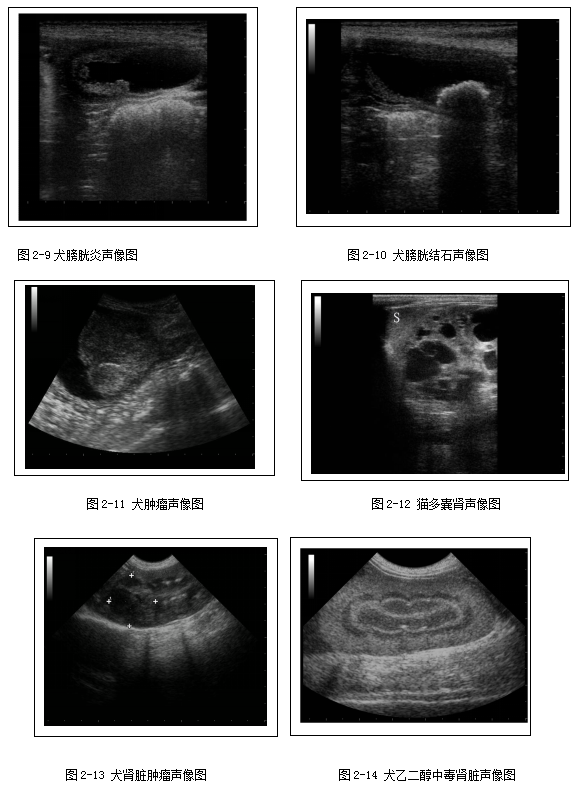

左右两侧肾脏大小相当;肾脏的包膜呈现为高回声;肾脏皮质回声强度略低于或等于肝脏回声,显著低于脾脏回声(2-5);肾脏髓质与皮质相比,髓质呈低回声结构(2-6)。猫的肾脏中由于皮质内脂肪细胞聚集,所以有时猫的肾脏皮质回声强度会高于肝脏回声。在肾脏矢状面上可显示中等回声的肾脊,其为肾髓质的延伸部分,与肾盂接触;此外肾脏矢状面上还可显示肾柱,为皮质向髓质内的延伸,将髓质分成一个个肾椎体(图2-7)。再略微靠近肾门处的肾脏矢状面,还可显示肾窦呈平行的两条高回声带状结构(图2-8)。弓形血管的管壁呈成对的、短线高回声结构,位于皮质髓质交接处。正常犬猫的肾盂偶尔可见,高分辨率的探头有助于肾盂的显影。正常犬猫的肾盂憩室和输尿管除非扩张,否则在超声上是不可见的。

泌尿系统超声检查主要用于评估膀胱的病变(图2-9、2-10、2-11)和肾脏损失(2-12、2-13、2-14、2-15、2-16),以及输尿管的扩张(图2-17)。